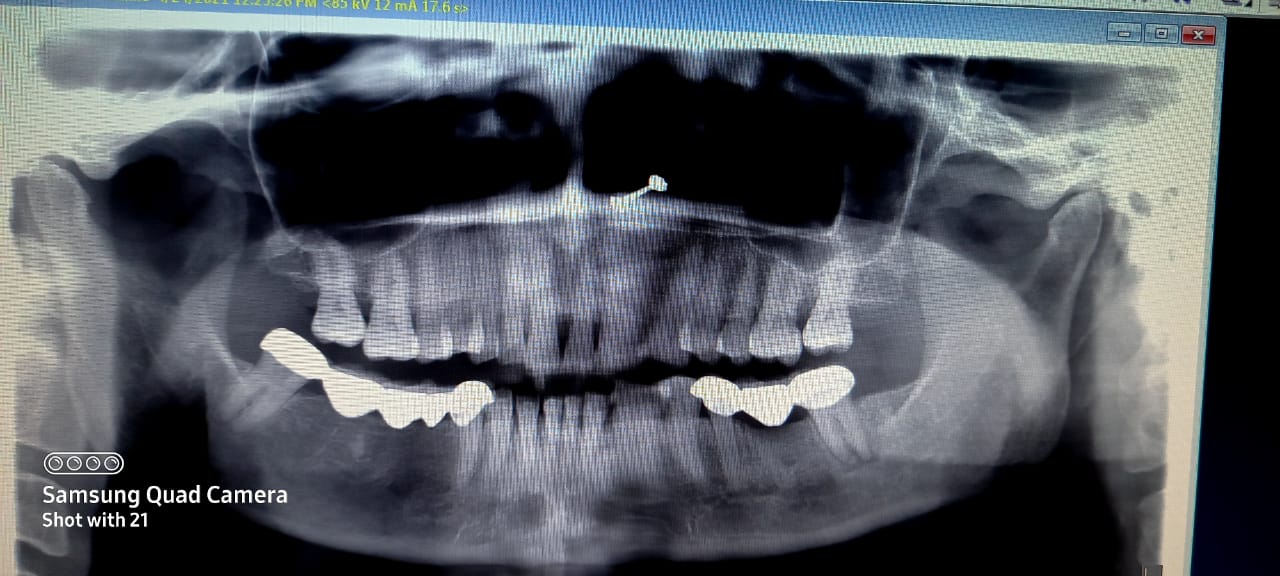

Aoa. Meri mother ki left side k nechay darh me taklef ha . Plz ye x-ray chk kR k bta den. Is there something to worry. Kuch din pehlay andr SE skin bohat red b ho gai thi. Phir pain killer se pain thek ho gai thi. Now again in pain

Ap xray ko zoom kr k dekhain pus nikalti hui nazar arahi he sath khoon bhi nazar araha he max zoom in kren

There seem to be some radioluceny but it can be verified clinically and pt symptoms. i recommend you should vist dentist and diagnosed it properly.

there seems multiple problems:

the bridge needs to be removed,

both, 5 & 7 need rct, there appears left out root of 6 (mesial root), it should be removed

upper 7 has deep distal cervical caries, it should be filled.

Is bridge mey sy cavity bna k daant ki root canals ka infection nikaalna hoga